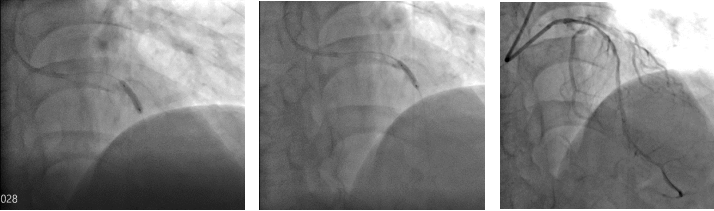

冲击波球

在楚天舒主任指导下,团队顺利使用Shockwave IVL震波球囊对钙化病变处进行多个周期的冲击波治疗。治疗中可见冲击波球囊逐渐扩张开顽固钙化区域,冲击波治疗后复查造影可见左前降支近中段的钙化狭窄处明显改善。术中植入的2枚药物洗脱支架在行IVUS中可见支架贴壁和膨胀良好,血管扩张成形满意。术中患者无明显不适,未见低血压、ST改变及心律失常,术后患者胸痛症状明显好转。目前,该患者病情平稳,胸痛症状完全缓解。

术后造影